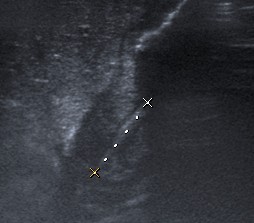

VisiónLongitudinal del píloro engrosado. Mide 18 mm aprox.

Visión longitudinal del píloro engrosado. Mide 18 mm aprox.

Se consideran diagnósticas un grosor de la capa muscular de 3 mm y una longitud del canal pilórico elongado de 14 mm. En general, ninguna de las medidas es tan importante, porque si el músculo está patológicamente engrosado, el canal estará elongado y fijo por el espasmo sin que se produzca una relajación del píloro para el paso de contenido desde el estómago al duodeno.